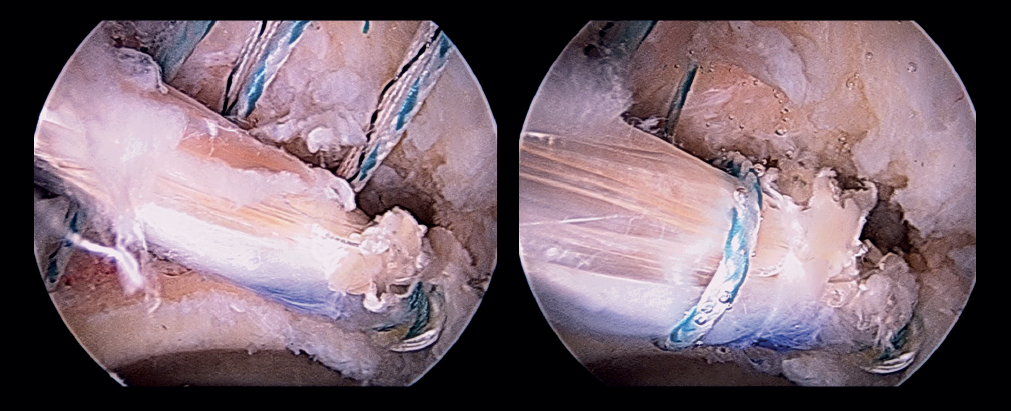

Once the anterolateral and modified anterior portals have been established, an interportal capsulotomy is performed to allow handling of the instruments within the joint. The vision portal during most of the surgery is the anterolateral portal. During the procedure a degenerated labrum is observed, with re-ruptures, adherences and an impaired chondrolabral junction. In addition, an important anterior capsule defect is observed. This combination clearly determines the loss of joint sealing (Figure 3). In a first step we remove the deficient labrum in the anterosuperior zone and the acetabular margin is gently refreshed with a 4.0 mm round bur (Stryker®) to expose the proximal anatomical insertion of the iliofemoral ligament: from the upper part of the iliopsoas recess (approximately in the 2:30 o'clock position) to the anteroinferior portion of the anteroinferior iliac spine (AIIS) (approximately in the 12 o'clock position). The remaining capsule tissue in the zona orbicularis(ZO) is refreshed with a synoviotome in preparation for the distal anastomosis. Then, the hip is examined through flexion and rotation to evaluate the capsule defect in these positions. Through the DALA we place two 2.1 mm PressFT® (Conmed) suture anchorings loaded with Hi-Fi number 2 suture in the acetabular margin proximal to the labrum, in the insertion zone of the iliofemoral ligament, at the 12 and 2:30 o'clock positions, and the sutures are exteriorized through the proximal middle anterior portal (PMA) (Figure 4). These sutures will be used for the acetabular or proximal insertion of the capsule dermal graft.

Figure 3. Right hip: arthroscopic view showing the combined labral and capsular deficiency. A: labrum; B: deficient capsule and capsule defect. View from the anterolateral port.

Figure 7. Arthroscopic view of segmental labral reconstruction with tibialis anterior allograft with fixation using knotless tensionable technology. View from the anterolateral port.